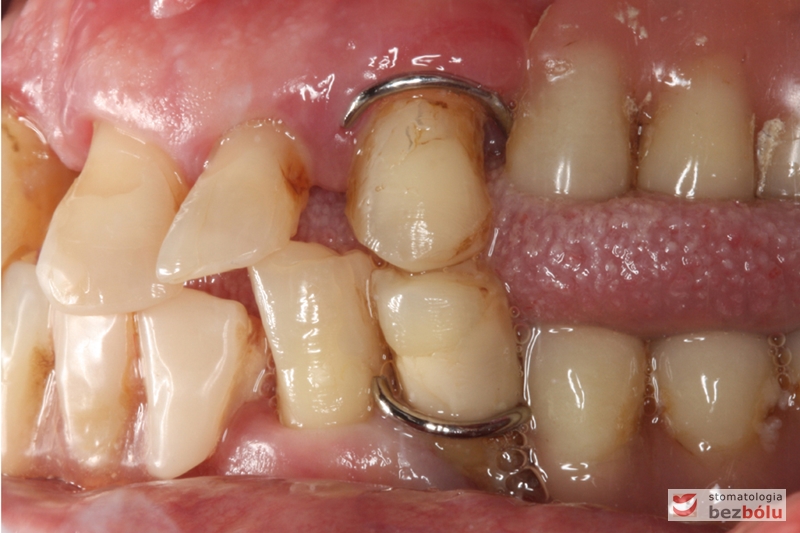

Gotowe patryce koron teleskopowych umieszczone w jamie ustnej na filarach zębów własnych